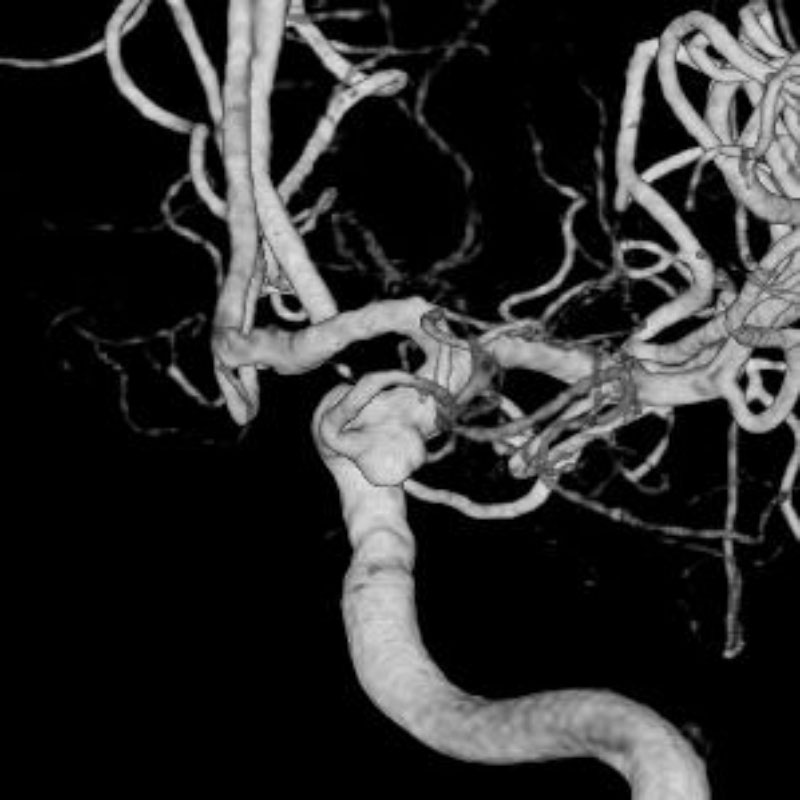

脳動脈瘤(Rt.IC-PC)

フローダイバーター留置術

芝野/古谷/木本